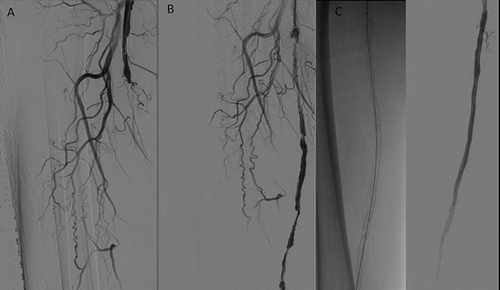

Απεικονιστικές εξετάσεις για τη διερεύνηση της διαλείπουσας χωλότητας αποτελούν το έγχρωμο duplex (triplex), η αξονική αγγειογραφία, η μαγνητική αγγειογραφία και η ψηφιακή αφαιρετική αγγειογραφία.

Σε περιπτώσεις διαλείπουσας χωλότητας μη περιοριστικού τύπου συνήθως η θεραπεία είναι συντηρητική. Αυτή περιλαμβάνει φαρμακευτική αγωγή, ρύθμιση παραγόντων κινδύνου, διακοπή του καπνίσματος και επιτηρούμενο πρόγραμμα άσκησης. Σε περιπτώσεις κρίσιμης ισχαιμίας ή σοβαρής διαλείπουσας χωλότητας η αντιμετώπιση είναι συνήθως επεμβατική, είτε με αγγειοπλαστική με ή χωρίς stent, ή χειρουργική.